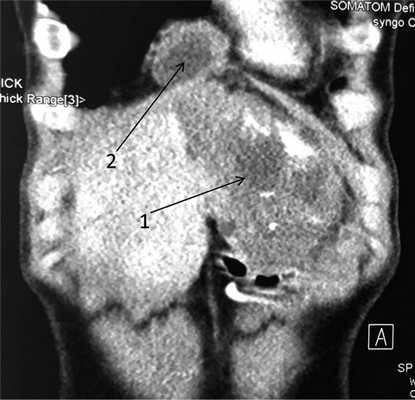

При поступлении общее состояние удовлетворительное, сознание ясное, кожный покров и видимые слизистые оболочки бледно-розовые, обычной влажности. Аускультативно дыхание в легких везикулярное, проводится во все отделы, хрипов нет. Язык влажный. Живот асимметричный из-за объемного образования, занимающего область правого подреберья и эпигастрия. При пальпации образование плотной консистенции, бугристое, безболезненное, малоподвижное. В общем анализе крови повышенная СОЭ — 23 мм/ч, других изменений, в том числе эозинофилии, нет. Биохимические показатели крови в пределах нормы. Уровень антител к антигенам гельминтов (эхинококк) в 4 раза превышает допустимые показатели (коэффициент позитивности 3,37 при норме менее 0,9). Для оценки ангиоархитектоники печени, а также для уточнения локализации объемного образования относительно магистральных сосудов и желчевыводящих путей пациентке выполнены МСКТ и МРТ. МСКТ: печень с ровными контурами, умеренно увеличена в размерах, косой вертикальный размер 18 см, в левой доле визуализируется объемное образование неправильной формы размером 84×105 мм с кальцинатом 33,5×40 мм. В артериальную фазу не накапливает контрастное вещество, в венозную и паренхиматозную фазы сохраняет низкие денситометрические показатели и приобретает четкие бугристые контуры за счет контрастирования окружающей паренхимы печени. В SVI сегменте визуализируется образование низкой плотности (15—11 ед. Н), неправильно округлой формы размером 26×30 мм, не накапливает контрастное вещество во все фазы исследования. На остальных участках паренхима печени однородной структуры до (56 ед. Н). Внутри- и внепеченочные желчные протоки не расширены. Над телом железы визуализируется кальцинат размером 20 мм (рис. 1). Рис. 1. МСКТ-грамма брюшной полости. Патологические образования в печени (1), поджелудочной железе (2).

Для определения объема резекции произведена оценка МСК-ангиограмм. В первую очередь интересовала возможность сохранения афферентного и эфферентного кровотока в здоровой части печени. При детальном исследовании правая и срединная печеночные вены по отношению к патологическому образованию интактны, при этом левая печеночная вена полностью вовлечена в патологический процесс (рис. 2). Рис. 2. МСКТ-ангиограмма брюшной полости (артериальная фаза).